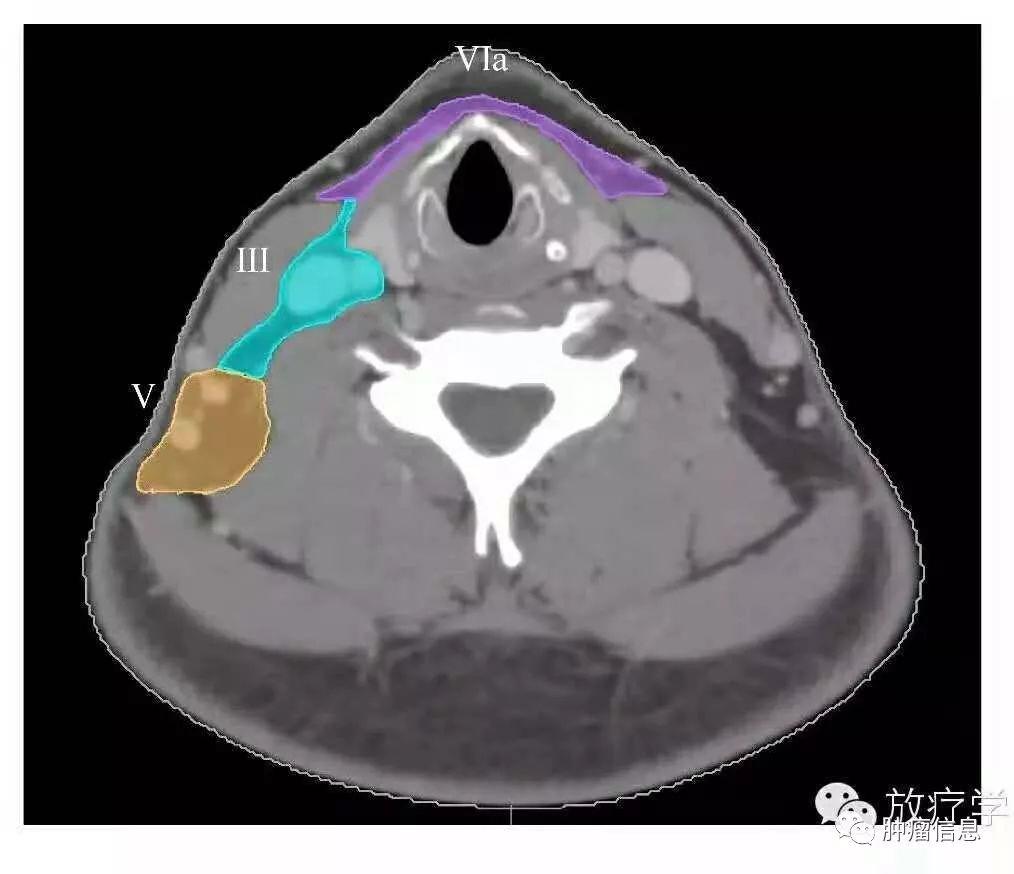

颈部III区淋巴结

上界:舌骨上缘下界:环状软骨下缘前界:胸骨舌骨肌侧后缘后界:胸锁乳突肌后缘内界:颈血管鞘内缘、头长肌外侧界:胸锁乳突肌内缘

颈部III区图中绿色为III区

颈部V区淋巴结

上界:颅底下界:锁骨上缘前界:胸锁乳突肌后缘后界:斜方肌前缘VA:环状软骨下缘以上区域VB:环状软骨下缘至锁骨上缘区域

颈部V区图中黄色为V区

颈部VI区淋巴结

颈前淋巴结上界:舌骨下界:胸骨切迹后界:颈动脉鞘前方

颈部VI区图中紫色区域为VI区(VIa、VIb)